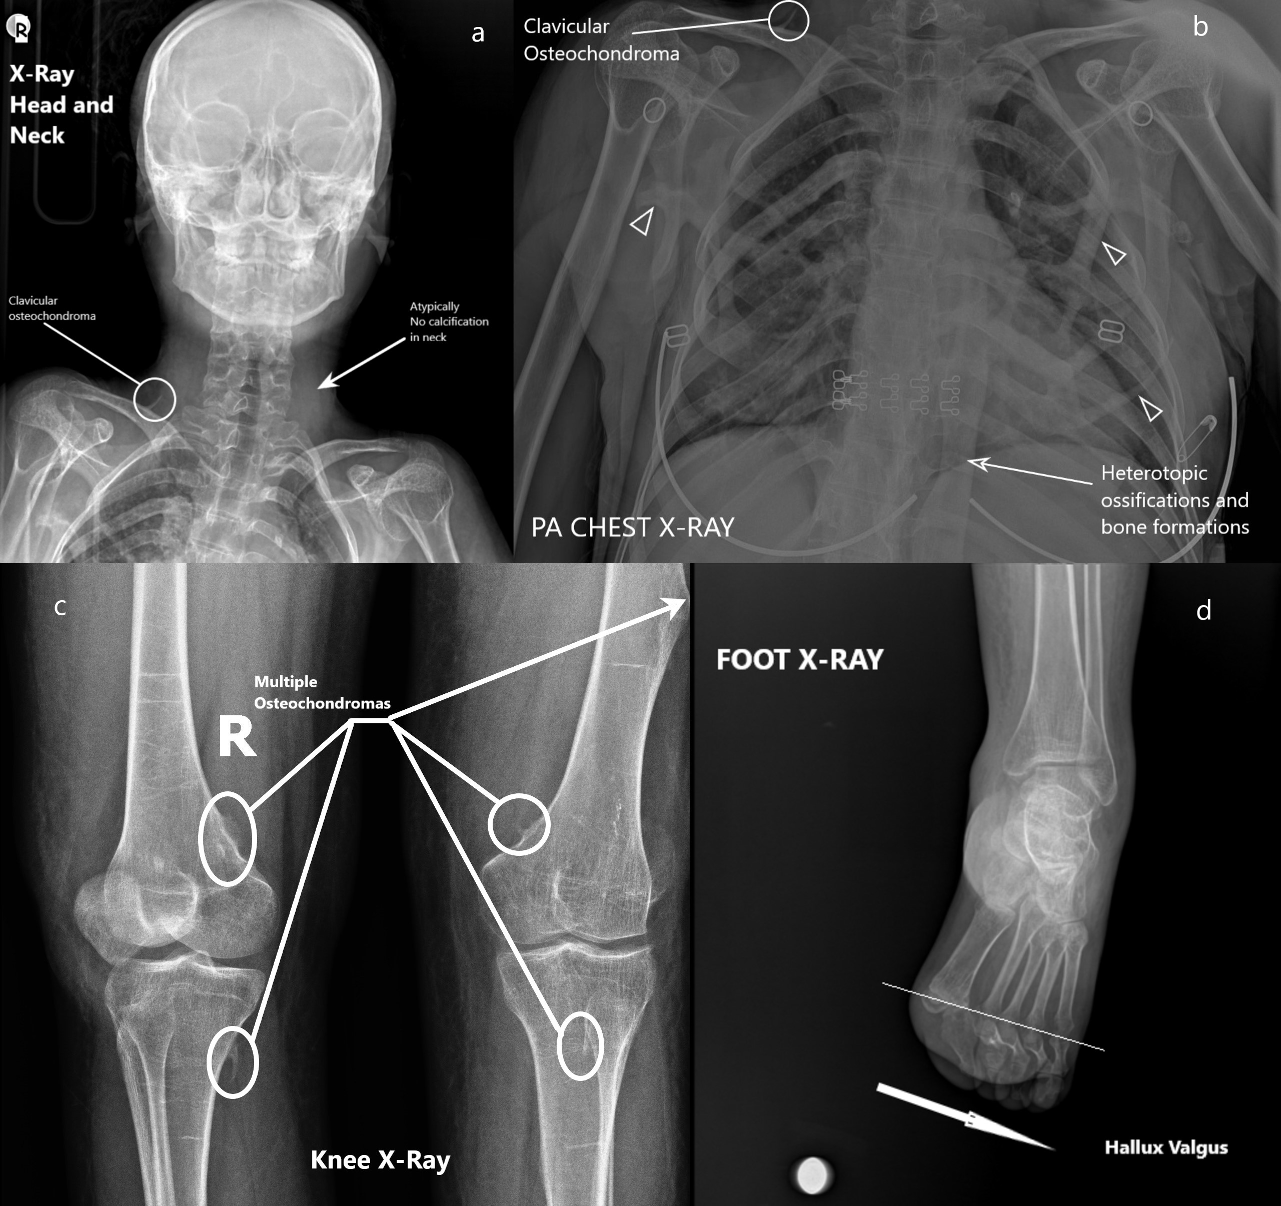

In the pulmonary and cardiac examination, respiratory sounds were bilaterally normal. No rales, rhonchi or pathological cardiac sounds (S1 + S2 + additional sound or murmur) were detected in the auscultation. The abdominal examination was also normal. No abdominal sensitivity, rebounds or defense was found. In the evaluation of the skeletal system from up to down, there was flattening in the neck. The shoulders’ abduction and left knee movement were limited. Difficulty in the extension of the waist and feet was present. Bilateral Babinski reflex was negative. Bilateral edema was present. Venous Doppler USG was requested. There was no vascular pathology. According to radiological algorithm, X-rays were taken first. Following the discovery of abnormalities, chest CT scans were performed. At the result of these evaluations, multiple linear heterotrophic bone formations that cover the chest were seen (paraspinal muscle calcifications). There were bridges between ectopic ossifications (Figure 1 [Fig. 1]). Scoliosis, ankylosis in bony structures and thickening of the paravertebral ligaments were present. Unlike the expected course of the disease, heterotopic neck ossifications were not detected (Figure 2a [Fig. 2]). Multiple osteochondromas in the right clavicle (Figure 1 [Fig. 1], Figure 2a [Fig. 2]), the posterior arch of the 9th rib (Figure 1 [Fig. 1]) with bridge ossifications (Figure 2b [Fig. 2]), metaphysis location of the right femur, distal diaphysis of the left femur, proximal metaphysis of the right femur, and fibula head (Figure 2c [Fig. 2]) were seen. Hallux valgus anomaly was present in both feet (Figure 2d [Fig. 2]). Table 1 [Tab. 1] shows common, ancillary and uncommon findings.

Figure 2: X-ray graphs; a) atypically no calcifications or ossifications in the neck, right clavicular osteochondroma; b) heterotopic ossifications and bone formations around the chest (arrowhead), compact bone formations along with vertebral axis, clavicular osteochondroma; c) multiple osteochondromas located around the knee joint; d) hallux valgus anomal